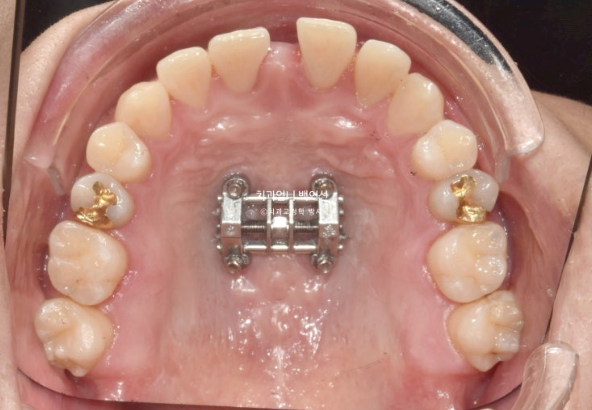

This is what it looked like in January 2023, one month after the initial visit, with the expansion device in place.

23.01

The palatal expansion device installed in the palate is not visible from the front.